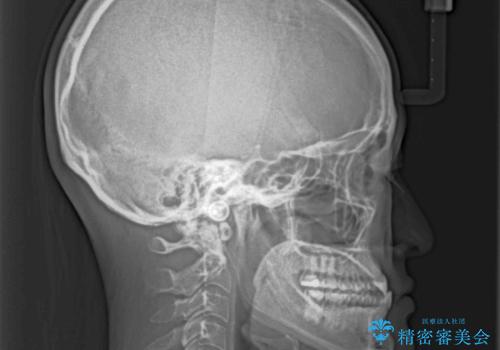

前歯のクロスバイトを治したい ワイヤー装置による矯正治療

- 前歯の反対咬合を気にして来院された患者様です。

マウスピース矯正も提案しましたが、しっかりと使用する自信がないとのことで、ワイヤー装置により矯正治療を行うこととしました。

クロスバイト改善まではスムーズに進みましたが、その後は強い舌の突出癖によりオープンバイトの期間が長く続きました。

舌のトレーニングをしっかりと実施してもらい、何とか仕上げることができました。